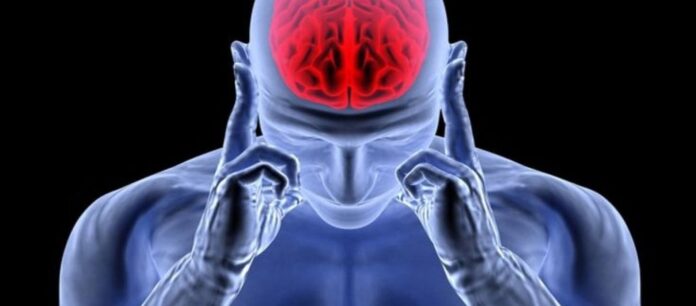

Αυτή είναι η βιταμίνη «ασπίδα» για το εγκεφαλικό επεισόδιο – Που θα την βρείτε

Όπως είναι ευρέως γνωστό, το εγκεφαλικό επεισόδιο αποτελεί ένα αιφνίδιο γεγονός το οποίο προκύπτει από βλάβη στη ροή του αίματος στον εγκέφαλο.

Τα συμπτώματα και οι επιπτώσεις του εγκεφαλικού εξαρτώνται από το τμήμα του εγκεφάλου που πλήττει και την έκταση της βλάβης που προκαλεί.

Η πρόληψη είναι πολύ σημαντική, προκειμένου κάποιος να ελαχιστοποιήσει τις πιθανότητες να υποστεί εγκεφαλικό. Μέρος αυτή είναι η κατάλληλη διατροφή και ειδικότερα η κατανάλωση μιας συγκεκριμένης βιταμίνης, η οποία σύμφωνα με τους επιστήμονες μπορεί να προστατεύσει από το αγγειακό εγκεφαλικό επεισόδιο.

Επιστήμονες από την Κίνα ανέλυσαν 14 κλινικές δοκιμές που πραγματοποιήθηκαν με τη συμμετοχή 55.000 ατόμων και διαπίστωσαν ότι η βιταμίνη Β μειώνει τον κίνδυνο εγκεφαλικού επεισοδίου κατά 7%.

Από αυτούς, οι 2.471 ασθενείς είχαν υποστεί εγκεφαλικό, όμως η βιταμίνη Β βοήθησε τον οργανισμό τους να μειώσει τα επίπεδα της ομοκυστεΐνης, ενός μορίου που εμπλέκεται στον σχηματισμό θρόμβων.

Σύμφωνα με τους επιστήμονες, η βιταμίνη Β μειώνει την ομοκυστεΐνη, άρα και τον κίνδυνο εγκεφαλικού επεισοδίου.

Η βιταμίνη Β αποτελείται από μια ομάδα οκτώ βιταμινών και υπάρχει στα δημητριακά, τον τόνο, τις μπανάνες, το συκώτι κ.α. Άλλες μελέτες έχουν δείξει ότι η βιταμίνη Β3 βοηθά τους ασθενείς που έχουν υποστεί εγκεφαλικό επεισόδιο να αναρρώσουν καλύτερα και ταχύτερα.

Σύμφωνα με τους επιστήμονες, η ικανότητα της βιταμίνης Β να μειώσει τον κίνδυνο εγκεφαλικού επεισοδίου επηρεάζεται από αρκετούς παράγοντες, όπως ο βαθμός στον οποίο απορροφάται από τον οργανισμό, τα επίπεδα του φολικού οξέος και της Β12 που υπάρχουν στο αίμα και η ύπαρξη υπέρτασης ή νεφρικών προβλημάτων.